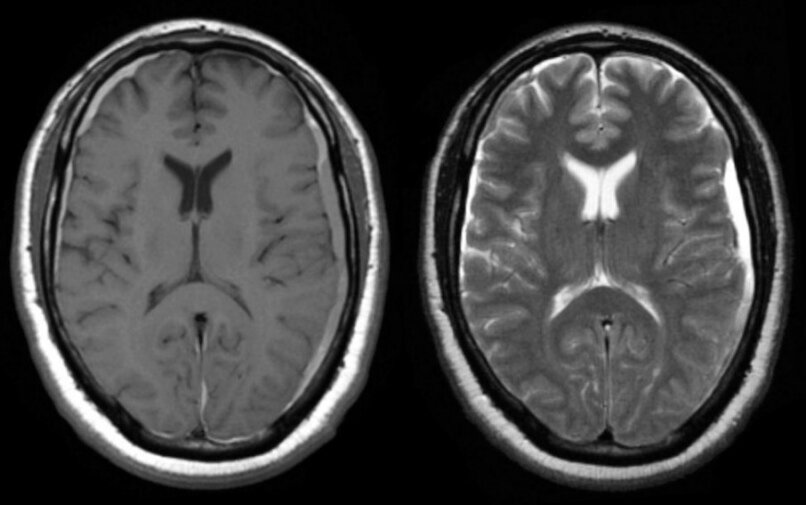

Hydrocephalus

Hydrocephalus is a build-up of fluid on the brain. The excess fluid puts pressure on the brain, which can damage it. The damage to the brain can cause a wide range of symptoms, including: headache being sick